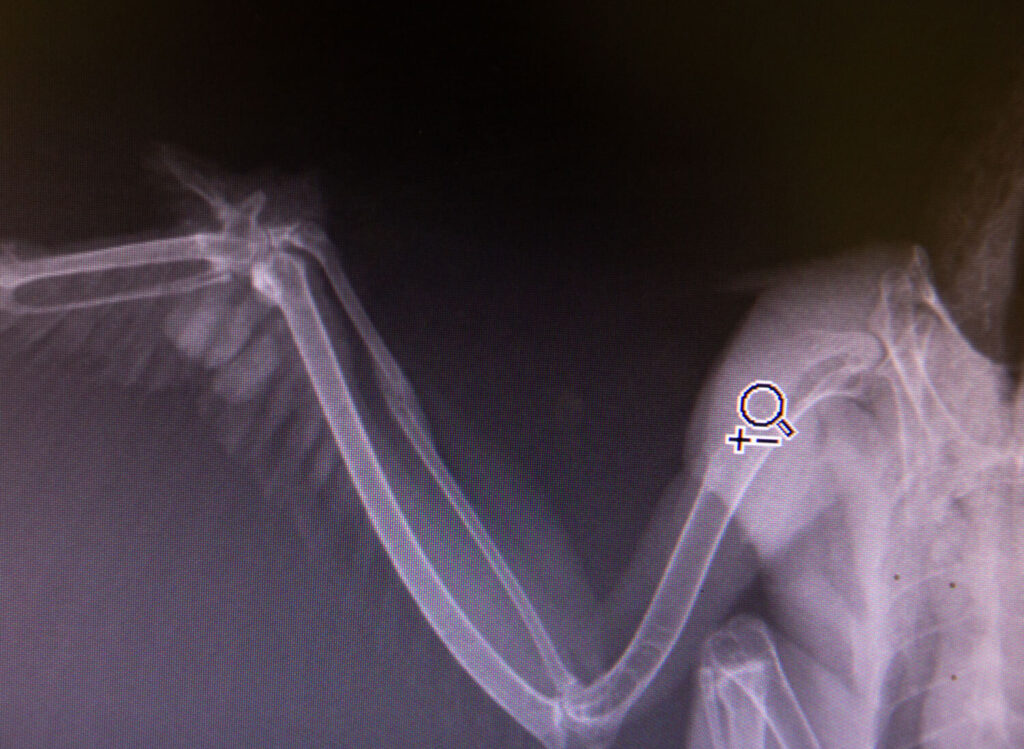

Understandably, cranky, he was admitted with an abscess on his right-wing joint, which volunteer vet Judith, was immediately concerned about. With crepitus also felt in the joint, an X-ray was needed to get to the bottom of the birds reason for grounding.

Whilst the X-ray revealed nothing obvious on the joint, it did show an old break to his radius, on the same wing.

Amazingly, this was already calcifying, but we suspect the abscess on the joint is preventing the bird from extending his wing properly and, thus, rendering him unable to fly.